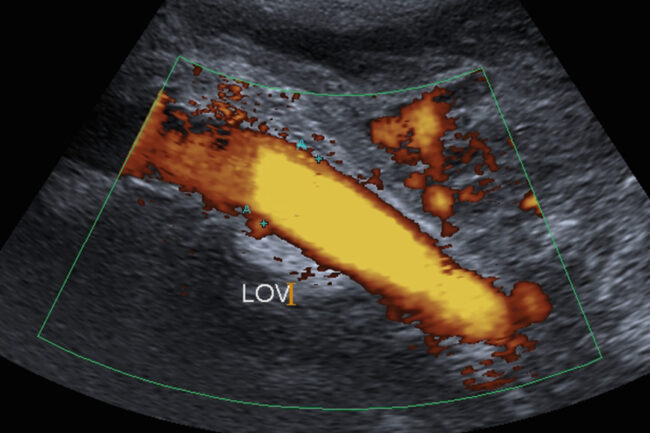

Dziś sytuacja wygląda zupełnie inaczej. Ultrasonografia dopplerowska (USG Doppler) stała się złotym standardem w diagnostyce żylnej – to nasze podstawowe narzędzie, które pozwala precyzyjnie ocenić stan Twoich żył przed rozpoczęciem jakiegokolwiek leczenia. Dzięki zaawansowanej diagnostyce obrazowej możemy nie tylko dokładnie zaplanować terapię, ale też sprawdzić jej skuteczność.

W przypadkach wymagających bardziej szczegółowej diagnostyki (tzw. diagnostyki rozszerzonej układu żylnego), stosuje się zaawansowane techniki obrazowania, takie jak: wenografia rezonansu magnetycznego (skrót ang. MRV) czy wenografia tomografii komputerowej (skrót ang. CTV). Ultrasonografia wewnątrznaczyniowa (skrót ang. IVUS) oraz flebografia cyfrowa są raczej metodami, po które sięgamy już w czasie wykonywania zabiegów naprawczych na układzie żylnym.